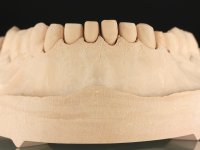

Realizado o diagnóstico e tomada a decisão quanto ao tratamento a executar, tornou-se importante definir qual a sequência de trabalho a adotar no sentido de conseguir a reabilitação da D.V.O. (V.D.O), de forma progressiva e equilibrada. Na primeira fase fez-se uma pré-impressão da arcada inferior com silicone tipo “putty” e em seguida realizou-se o preparo dentário de todo o sector posterior. O preparo para os overlays foi feito coronalmente à linha amelo cementaria no sentido de ser o mais conservador possível. A impressão foi feita com técnica de dupla mistura após afastamento gengival realizado com pasta de caulino. A provisória foi realizada com resina composta de polimerização dual. Em laboratório foram realizados os overlays após se ter aberto ligeiramente (1,5mm) a D.V.O. nos modelos montados em articulador semi-ajustável. Simultaneamente o sector antero-inferior foi encerado no sentido de acompanhar este aumento da D.V.O. Também foi confecionada uma chave de silicone translucido para posterior confeção dos provisórios antero-inferiores. Em boca foi primeiro realizada a provisionalização dos dentes anteriores utilizando resina composta previamente aquecida após preparação das superfícies dentárias para a adesão. Foi colocado o dique de borracha para promover o isolamento absoluto e posteriormente foram colados os overlays. Em laboratório foi realizada nova chave de silicone para confecionar os provisórios antero-superiores. Seguidamente em boca foram preparados os seis dentes antero-superiores após colocação do fio de afastamento gengival. Feita a preparação adequada das superfícies dentárias foi realizada a impressão com técnica de dupla mistura e a respetiva provisória. Em laboratório foram confecionadas 6 facetas feldespáticas num modelo de trabalho tipo “Geller”. A provisória foi removida e as facetas foram coladas em boca utilizando um isolamento relativo competente. Esta opção foi tomada em virtude de uma prévia experiencia negativa com a colocação do dique de borracha na mandibula. Após a colagem dos laminados antero-superiores foram dadas 12 semanas para avaliar a adaptação do paciente à nova situação e então iniciar a confeção das facetas antero-inferiores. Após colocação do fio de afastamento gengival. foram feitos os preparos dentários adequados e em seguida foi feita a impressão. Também foi feita a preparação do dente 3.4 que, entretanto, tinha sofrido uma fratura do overlay. As facetas e a restauração do 3.4 foram realizadas num modelo de trabalho tipo “Geller”. Após remoção da provisória, as facetas foram coladas em boca, utilizando um isolamento relativo pelas razões apontadas anteriormente. Após colocação do trabalho o paciente foi reabilitado por outros colegas com um implante na zona do 2.6 e substituição da coroa aparafusada sobre o implante colocado no local do 3.5. Posteriormente surgiram fraturas nos overlays dos dentes 4.7 e 3.7 que foram reabilitados com overlays em Zr.